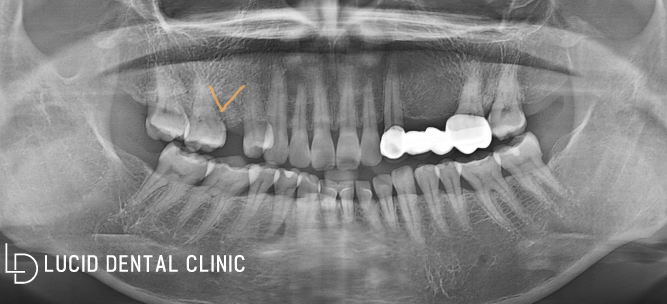

먼저 전체 구강 환경을 파악할 수 있도록

초진 파노라마 사진 촬영부터 시행했는데요

브릿지 수복을 받은 것과

이미 타원에서 발치를 받은

흔적을 발견할 수 있었습니다.

그러나, 제거하고 아무런

처치를 받지 않은 상태였는데요

현재 뒤쪽 치아를 자세히 보면 살짝 누워있기 때문에

임플란트 수술 을 시행하게 되면 조금 다듬어서

공간을 확보한 다음, 픽스처를 심어야 됩니다.